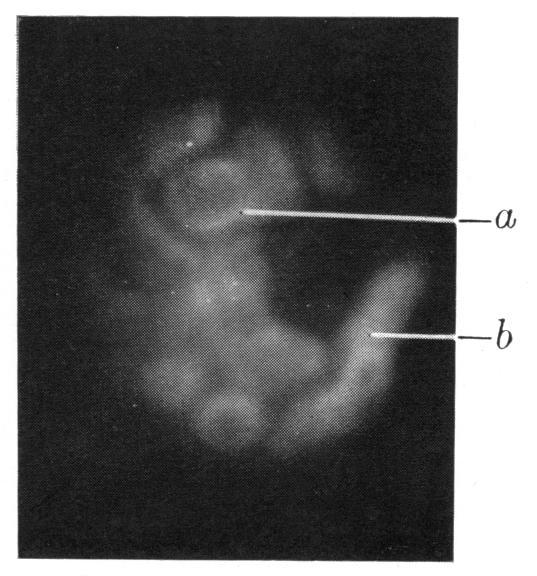

Lyochromes in the kidney. With a note on the quantitative estimation of lyochromes.

Biochem J. 1938 Feb;32(2):376-382.1. doi: 10.1042/bj0320376.